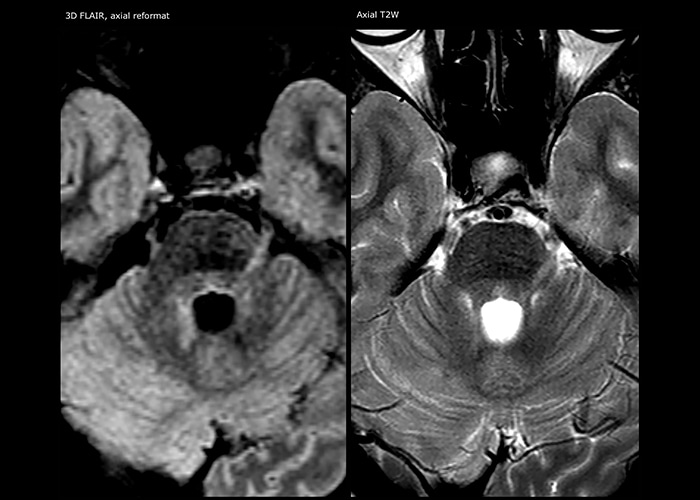

APT imaging of low-grade tumor. Low-grade glioma in a pre-teen patient with neurofibromatosis 1. This low-grade lesion does not enhance on the post-contrast images, but does show an intermediate APT signal. The lesion stability over time confirms that it is a low-grade pathology.